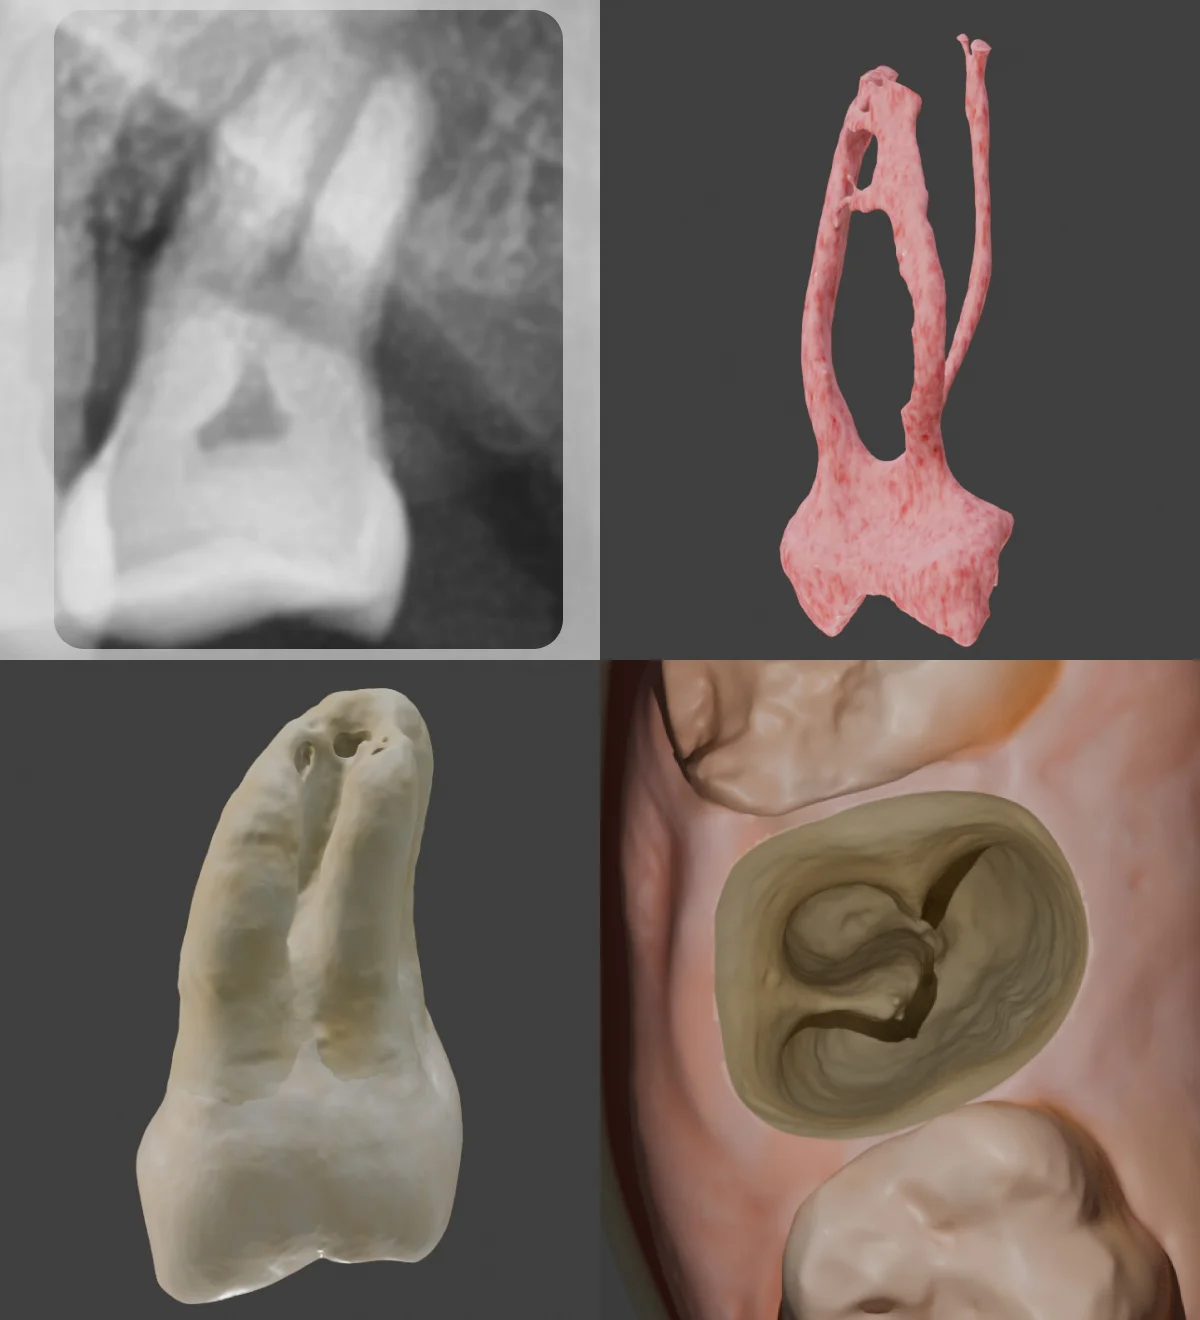

🔹 C-Shaped Root

One of the newly added teeth features a C-shaped root, but interestingly, the canals are still separated into MB, DB, and P. Notably, the MB and P canals are connected by an isthmus. Understanding this before treatment can help you optimize your access cavity design and improve irrigation effectiveness.